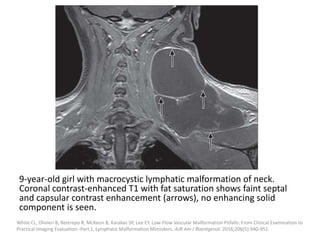

9-year-old girl with macrocystic lymphatic malformation of neck.

Coronal contrast-enhanced T1 with fat saturation shows faint septal

and capsular contrast enhancement (arrows), no enhancing solid

component is seen.

White CL, Olivieri B, Restrepo R, McKeon B, Karakas SP, Lee EY. Low-Flow Vascular Malformation Pitfalls: From Clinical Examination to